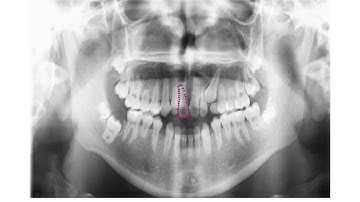

Dentition recognition using active shape model